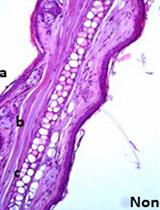

Clostridium difficile (a Gram-positive, spore-forming, strict anaerobe) can colonize antibiotic-treated hosts (McFarland, 2008). Antibiotics alter the composition of the normal, benign microbial flora which leads to loss of colonization resistance (Wilson and Perini, 1988; Antonopoulos et al., 2009). C. difficile spores germinate to actively growing bacteria which secrete toxins that damage the colonic epithelium (Voth and Ballard, 2005). The use of animal models of C. difficile disease have allowed the identification of mechanisms of colonization and virulence factors (Lyras et al., 2009; Kuehne et al., 2010; Francis et al., 2013; Aubry et al., 2012; Carter et al., 2011). This protocol describes virulence studies of C. difficile in the hamster model of C. difficile infection (Bartlett et al., 1978; Sambol et al., 2001).